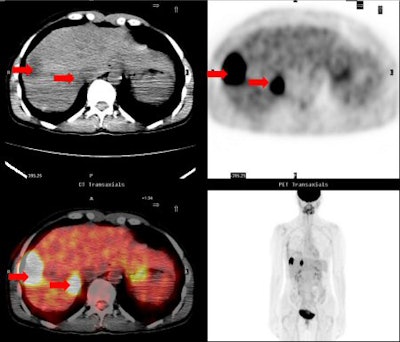

![]() |

| A 42-year-old woman with infiltrating ductal carcinoma. Postoperative (14 days) PET/CT demonstrated liver metastases (arrows). All images courtesy of Stanford University Medical Center. |